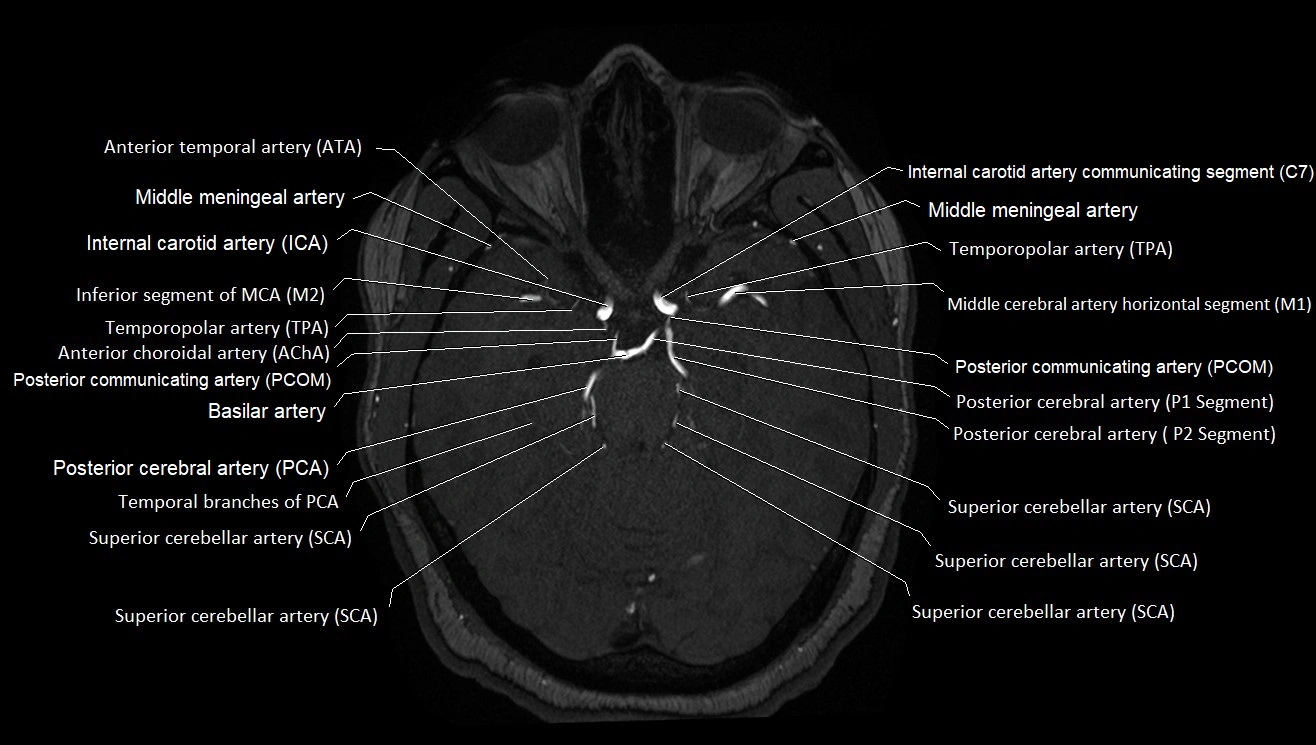

MRA (Magnetic Resonance Angiography):

• Flow-related enhancement makes the AChA appear as a bright, linear vascular signal against suppressed background

• High sensitivity for origin and proximal course; distal branches may be too small to resolve

• Detects stenosis, occlusion, aneurysm, AVM feeders

MRI images

image